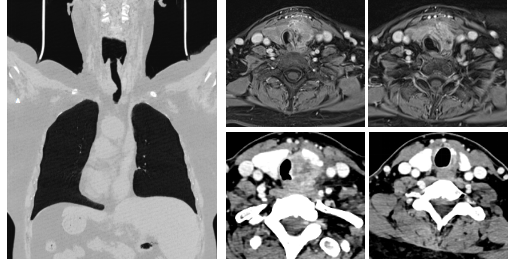

入院后,我们围绕病灶性质、受累器官等开展相关检验检查,影像学发现肿瘤侵犯气管气管高度45mm、侵犯气管环周长1/2以上、最窄平面宽度5.66mm、最窄平面距声门30mm。除此之外,环状软骨、食管肌层、喉返神经不同程度的受到侵犯。与此同时,甲状腺穿刺活检提示乳头状癌,气管活检病理会诊提示气管粘膜甲状腺乳头状癌浸润,因此术前诊断为局晚期甲状腺恶性肿瘤。诊断明确了,那么如何治疗呢?

肿瘤侵犯气管、食管、环状软骨